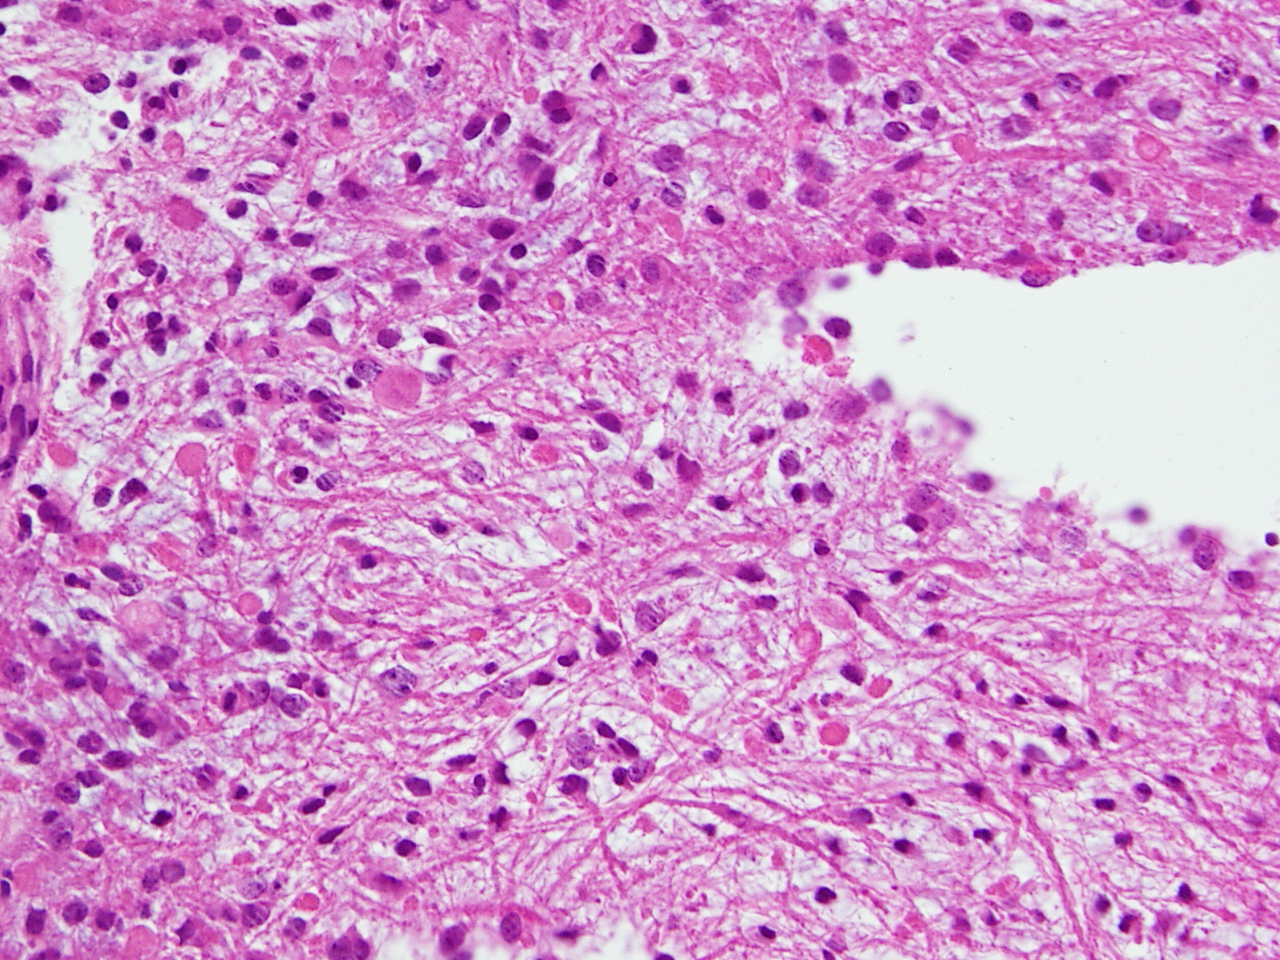

毛様類粘液性星細胞腫の病理像です。関質が広くて粘液用の物質が貯留されています。これは手術で取る時にドロドロの腫瘍に見えますから,ちょっと硬い普通の毛様細胞性星細胞腫とは判別できます。この病理像をもつ腫瘍は,患者さんの年齢が年長児になっていくと,自然に変化して普通の毛様細胞性星細胞腫に変わっていきます。腫瘍も年をとるのだと考えられます。ですから,毛様類粘液性星細胞腫は特殊なものではなくて,毛様細胞性星細胞腫の赤ちゃんです。右側の画像では,血管中心性に腫瘍細胞が配列するangiocentric patternがみられます。